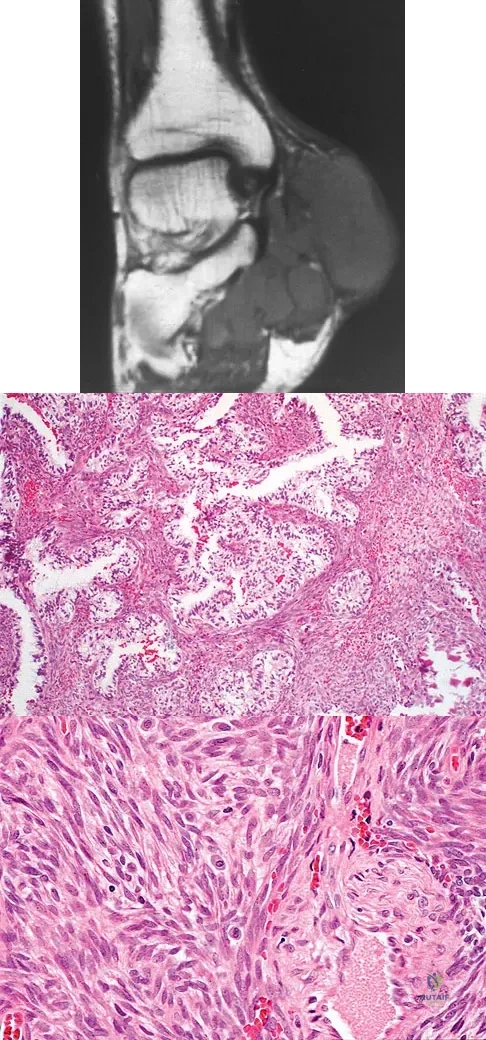

A 40-year-old man has a painless mass around his left ankle. He notes minimal growth over the past year. An MRI scan is shown in Figure 73a, and biopsy specimens are shown in Figures 73b and 73c. What is the most likely diagnosis?

Explanation